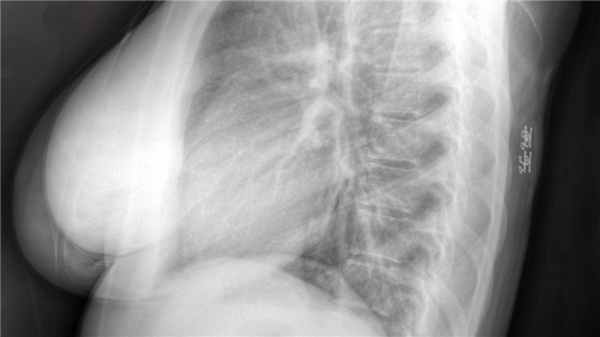

Обзорные спондилограммы пояснично-крестцового отдела в большинстве случаев показывают расщепление дужек (по определению должно быть практически во всех случаях, но в некоторых случаях вместо этого имеет место сегментирование). Также могут быть обнаружены аномальные соединения позвонков и дефекты крестца.

КТ/миелография или МРТ могут выявить ненормально низко расположенный конус. МРТ также показывает жировое объемное образование (высокий сигнал в режиме Т1, низкий в режиме Т2).